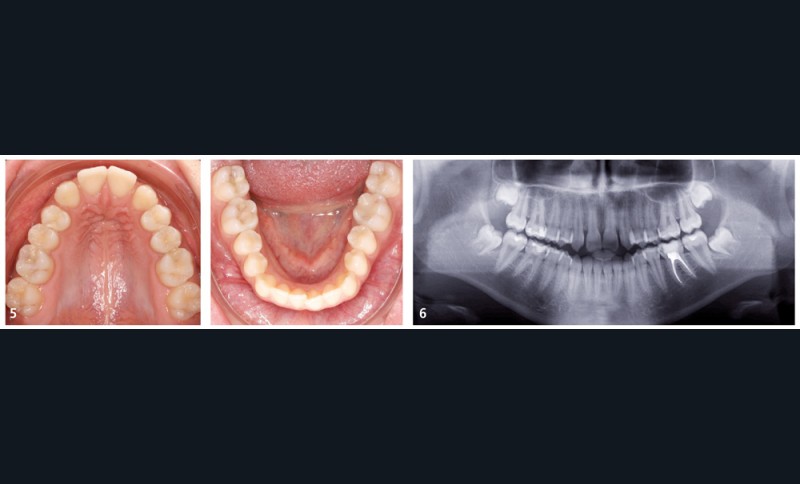

La jeune patiente présente, à l’examen clinique extra-oral, une tendance classe III qui se traduit par une protrusion de la lèvre inférieure de profil, et un menton très présent lors du sourire (fig. 1). À l’examen intra-oral, l’arcade maxillaire est en V, les incisives latérales permanentes droite (12) et gauche (22) sont manquantes et les espaces presque refermés. À l’arcade mandibulaire, un léger encombrement incisif est présent. En occlusion, elle présente une classe I molaire et canine et une occlusion inversée antérieure qui se prolonge à droite sur la première prémolaire (14) (fig. 2 à 5).